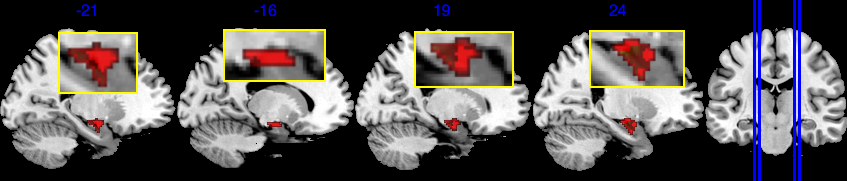

For a visual representation, Figure 3(a) shows the voxel level PIP in the sagittal plane. The highlighted red regions represent voxels with greater than 0.95 PIP. Figure 3(b) presents the effect size of , with the highlighted area in the range . Note that from Figure 3(b), voxels with PIP greater than 0.95 also correspond to voxels with a larger absolute value of effect size. We notice that the activation region (defined by voxel level PIP greater than 0.95) has a negative effect . This can also be validated by the scatter plot in Section D in the Supplementary Material, where the image intensity generally has a negative association with age across all individuals.

Based on our results, we have the following general interpretations: (i) when controlling for the confounders, age has a negative impact on the neural activity for emotion-related tasks; (ii) the negative effect reflected from each voxel is of very small scale, shown as in Figure 3(b), indicating a very low voxel level signal-to-noise ratio; (iii) the top 5 brain regions with the highest RLAR are (a) right intracalcarine cortex, right supracalcarine cortex, and left Temporal fusiform cortex, anterior division, all considered as critical areas for high-level visual processing including face recognition; (b) left temporal fusiform cortex, anterior division, a key structure for face perception, object recognition, and language processing (Weiner and Zilles, 2016); and (c) right inferior temporal gyrus, anterior division, an area for language and semantic memory processing, visual perception, and multimodal sensory integration (Onitsuka et al., 2004). These top 5 regions are also consistently identified in the sensitivity analysis when using half of the data as training data, see Section 4.4.1.

The amygdala region is part of the limbic system. They are responsible for detecting danger and negative emotions, and play an important role in behavior, emotional control, and learning (Bzdok et al., 2013). The emotion task fMRI data in UK Biobank is based on emotion tasks where participants are asked to identify faces with negative emotions. Hence we expect the amygdala region to play an important role. The amygdala region is a small area in the brain, as shown in Figure 4(a), containing 380 voxels out of a total of 121,865 voxels.

Based on the results shown in Figure 4, SBIOSimp identifies a large proportion of voxels in the amygdala region to be active. Numerically, SBIOSimp identifies 324 out of 380 voxels in both the left and right amygdala to be active with . From the highlighted box in Figure 4(b), the active voxels mostly concentrate on the direction where the amygdala region connects to the parahippocampal gyrus, anterior division. The anterior portion of the parahippocampal gyrus is involved in complex emotive processes and has significant interconnectivity with other cortical limbic structures and the amygdala (Kaas, 2016). Figure 4(c) shows the yellow-shaded area within the amygdala in which voxels are associated with at least 50% decline in the brain signal intensity for 10-year increase in age from 50.